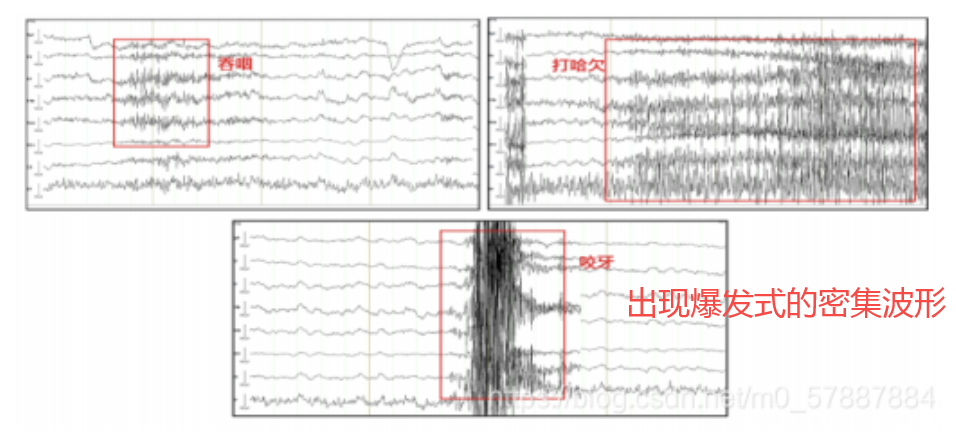

肌电伪迹是由头面部或颈部肌肉活动(如额肌、颞肌、颈肌等)产生的电信号,混入脑电图中形成干扰。

- 与眼电伪迹不同,肌电伪迹通常 频率高、波幅不规则 。

- 常出现在 EEG 采集过程中受试者紧张、皱眉、咀嚼、说话或头部移动时。

来源:额肌活动(皱眉、抬眉)、颞肌或颈肌(咀嚼、说话、吞咽、颈部张力)、头部动作(抖动、翻身)……